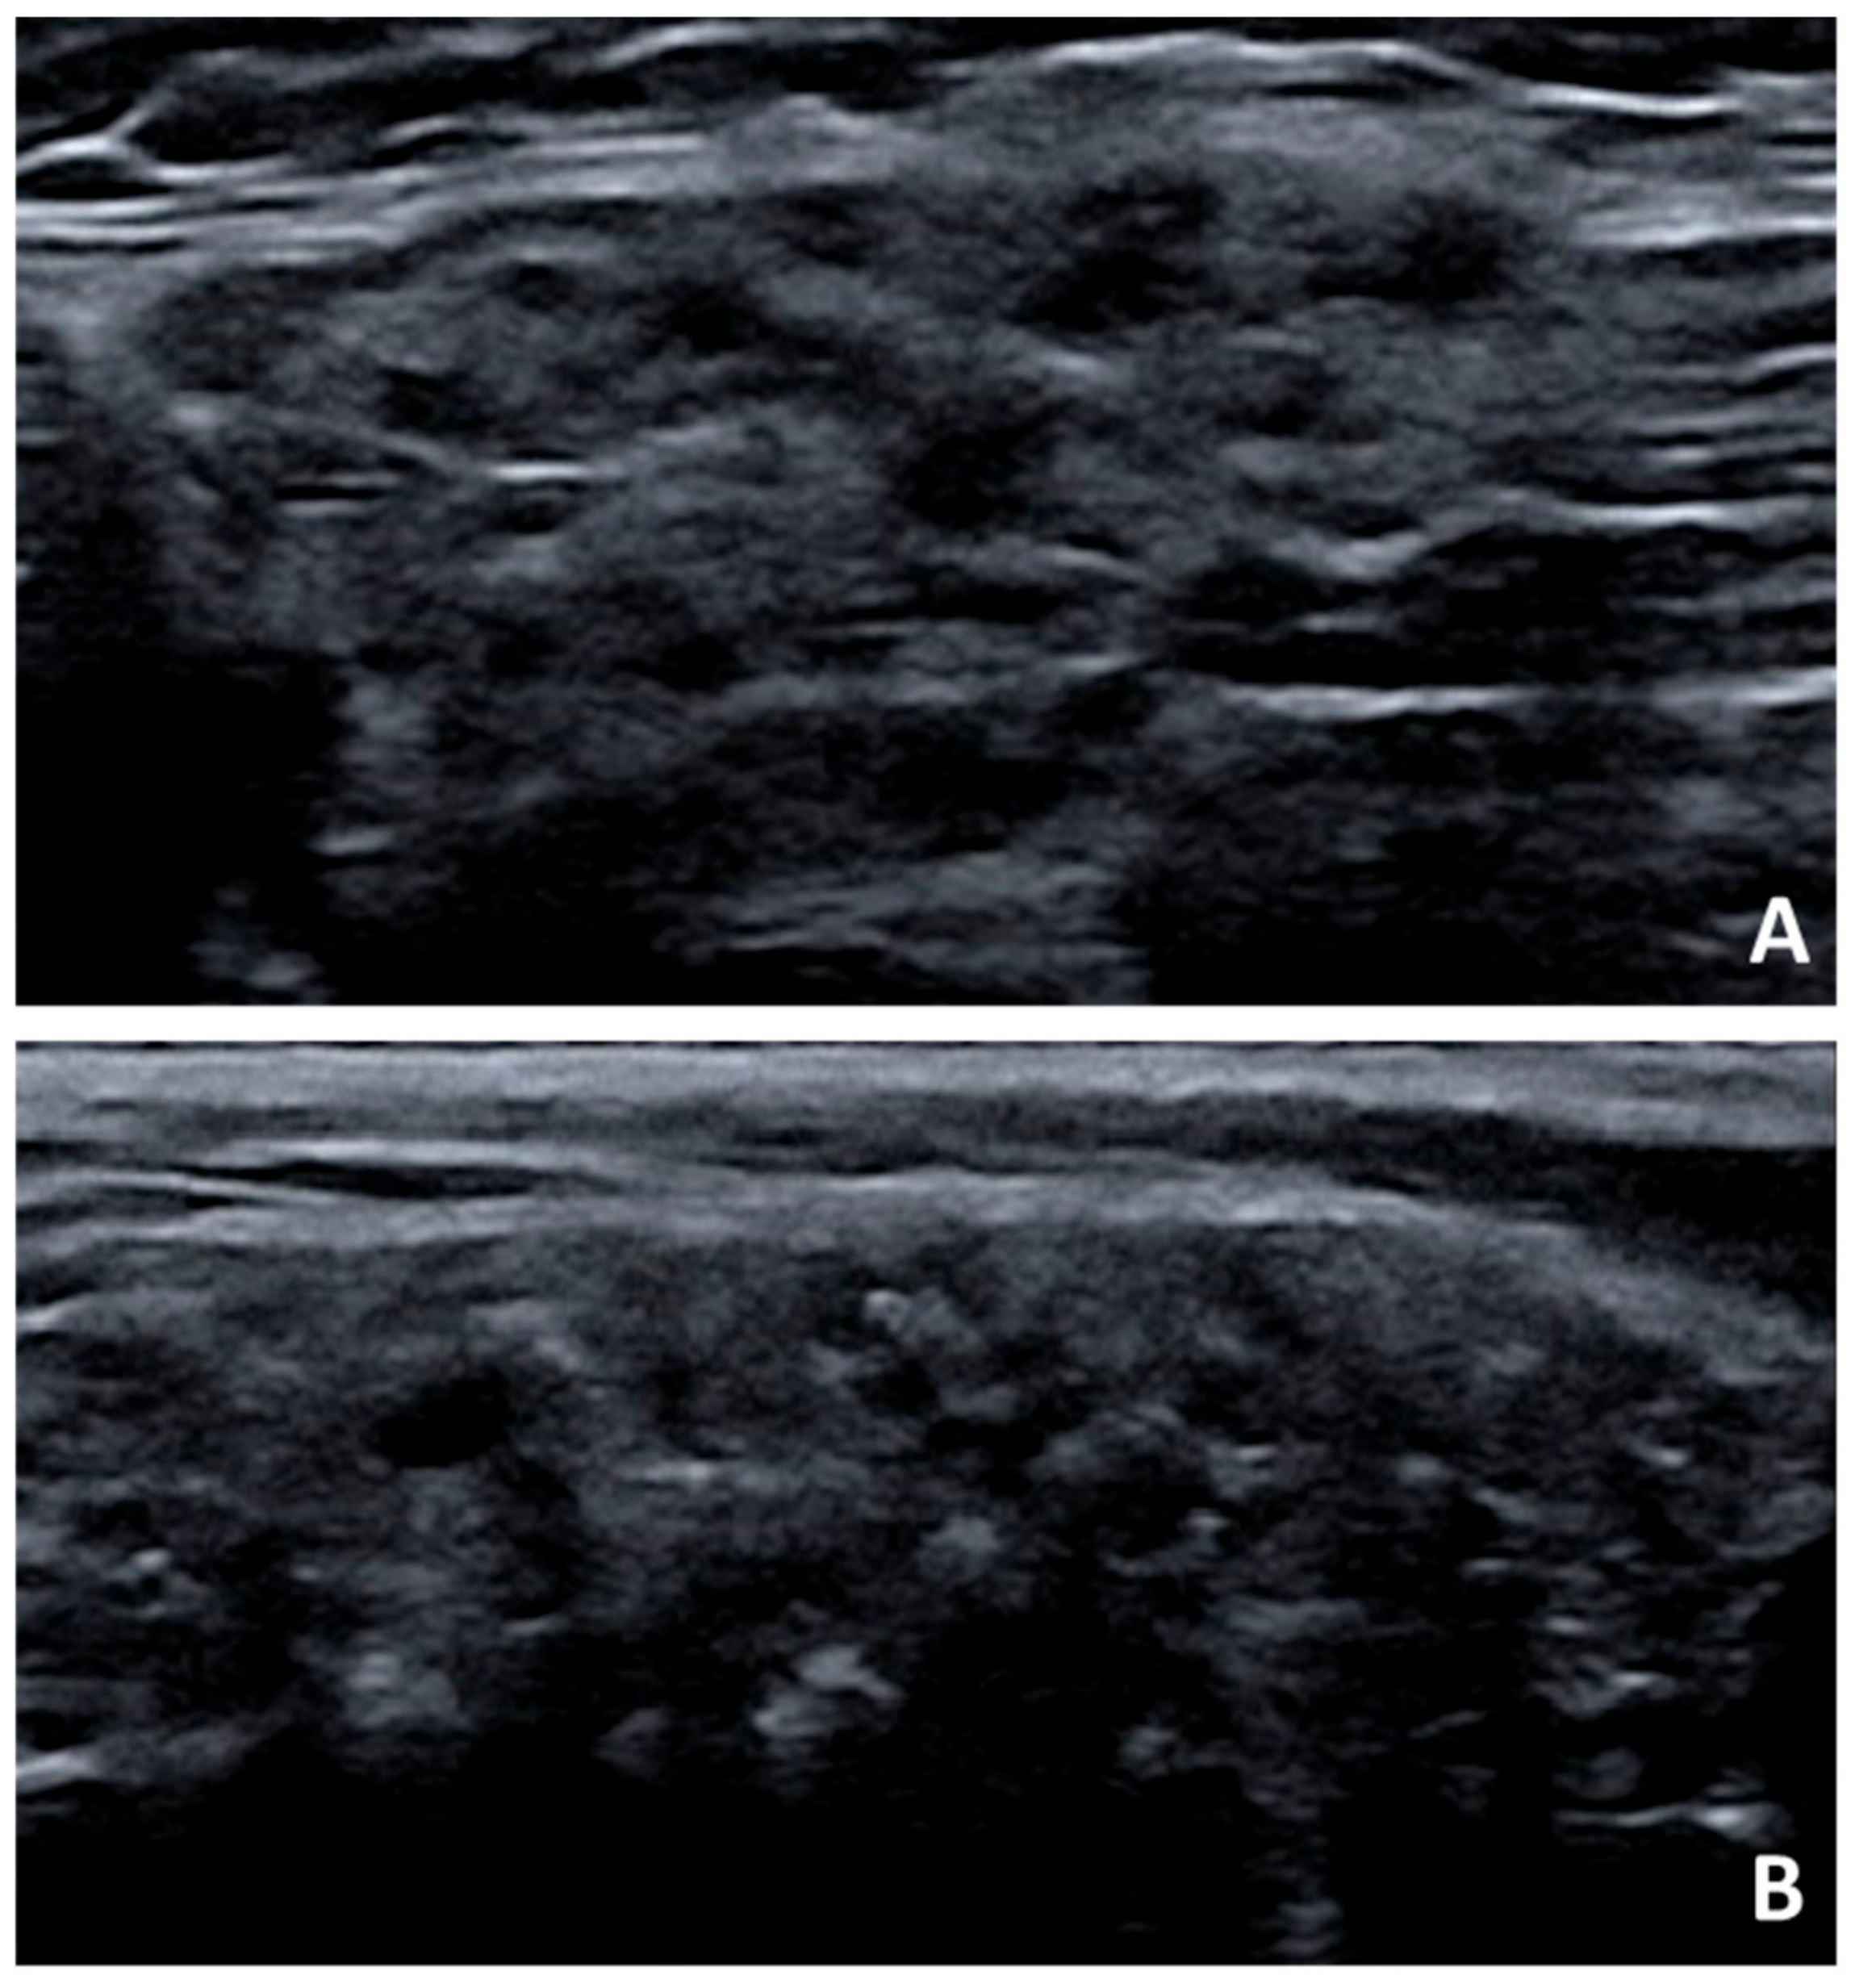

- Carotti, M.; Salaffi, F.; Di Carlo, M.; Barile, A.; Giovagnoni, A. Diagnostic value of major salivary gland ultrasonography in primary Sjögren’s syndrome: The role of grey-scale and colour/power Doppler sonography. Gland Surg. 2019, 8, S159–S167. [Google Scholar] [CrossRef]

- Devauchelle-Pensec, V.; Zabotti, A.; Carvajal-Alegria, G.; Filipovic, N.; Jousse-Joulin, S.; De Vita, S. Salivary gland ultrasonography in primary Sjögren’s syndrome: Opportunities and challenges. Rheumatology 2019, in press. [Google Scholar] [CrossRef]

- Jousse-Joulin, S.; D’Agostino, M.A.; Nicolas, C.; Naredo, E.; Ohrndorf, S.; Backhaus, M.; Tamborrini, G.; Chary-Valckenaere, I.; Terslev, L.; Iagnocco, A.; et al. Video clip assessment of a salivary gland ultrasound scoring system in Sjögren’s syndrome using consensual definitions: An OMERACT ultrasound working group reliability exercise. Ann. Rheum. Dis. 2019, 78, 967–973. [Google Scholar] [CrossRef] [PubMed]

- Mossel, E.; Arends, S.; Van Nimwegen, J.F.; Delli, K.; Stel, A.J.; Kroese, F.G.M.; Spijkervet, F.K.L.; Vissink, A.; Bootsma, H. Scoring hypoechogenic areas in one parotid and one submandibular gland increases feasibility of ultrasound in primary Sjögren’s syndrome. Ann. Rheum. Dis. 2018, 77, 556–562. [Google Scholar] [CrossRef] [PubMed]